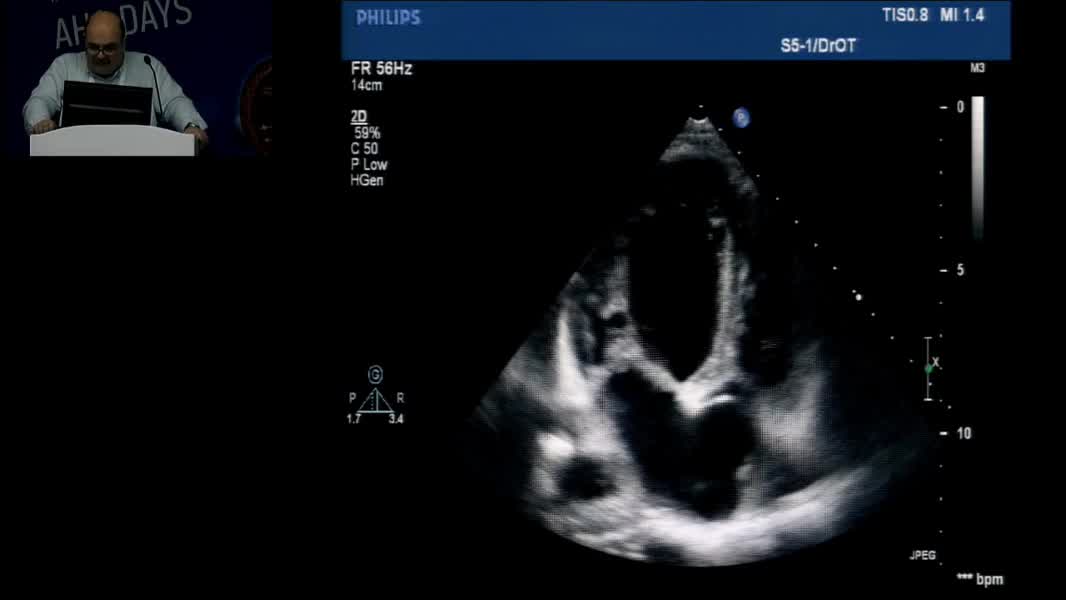

Echocardiographic Face Of Rare Cardiomyopathy And Fabry: Hands On Practical Echocardiography Course In The Diagnosis Of Fabry Disease And Cardiomyopathy Omaç Tüfekçioğlu (TR)

Nadir Miyokardiyopati ve Fabry’nin Ekokardiyografik Yüzü